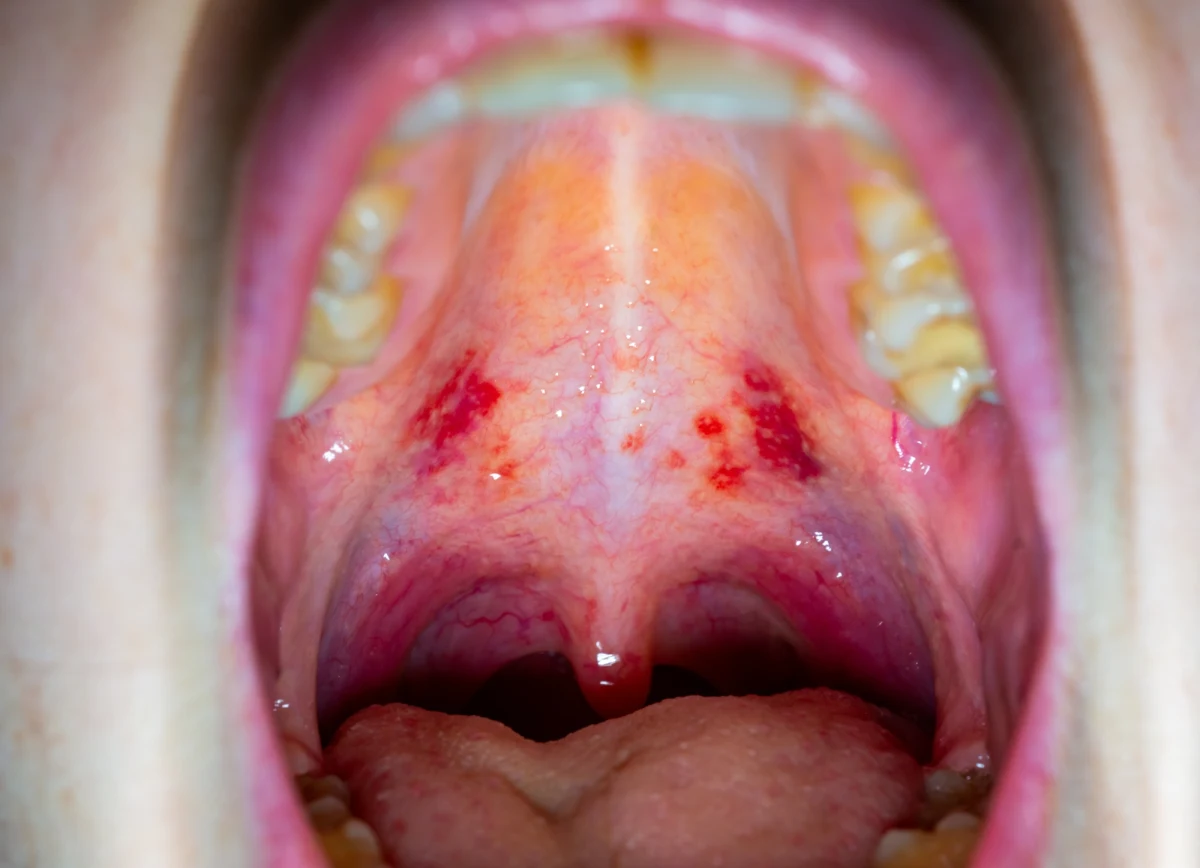

Wariant Nimbus (NB.1.8.1) powoduje wyjątkowo silny ból gardła, często opisywany przez pacjentów jako "żyletki w gardle". Może też wywoływać objawy ze strony układu pokarmowego, takie jak nudności, biegunki czy zaparcia.